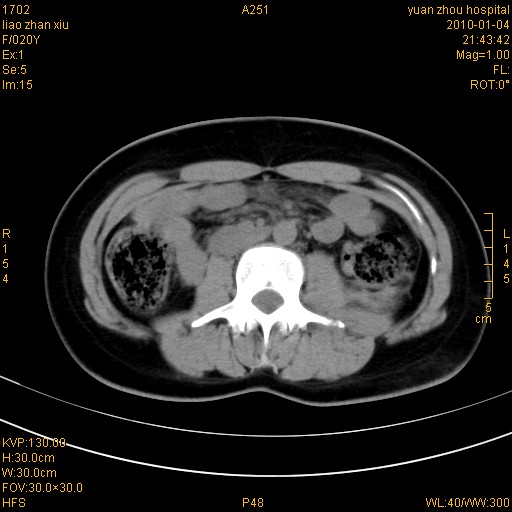

标题: CT23985:F20Y 外伤典型病例

左肾挫伤,包膜下积血。

左肾挫裂伤伴肾被膜下积血!另:肾周筋膜增厚!

1)左肾包膜下血肿。2)左侧肾挫伤可能;建议:行ct增强扫描检查。3)腰椎左侧横突骨折。

左肾挫伤,包膜下积血,l3、4左侧横突多发骨折。

双侧肾胞膜下出血,左侧较多。l3、4左侧横突多发骨折。

1、左肾挫伤,包膜下积血;

2、l3、4左侧横突多发骨折;

左肾挫伤,包膜下积血,L1、2、3、4左侧横突多发骨折。